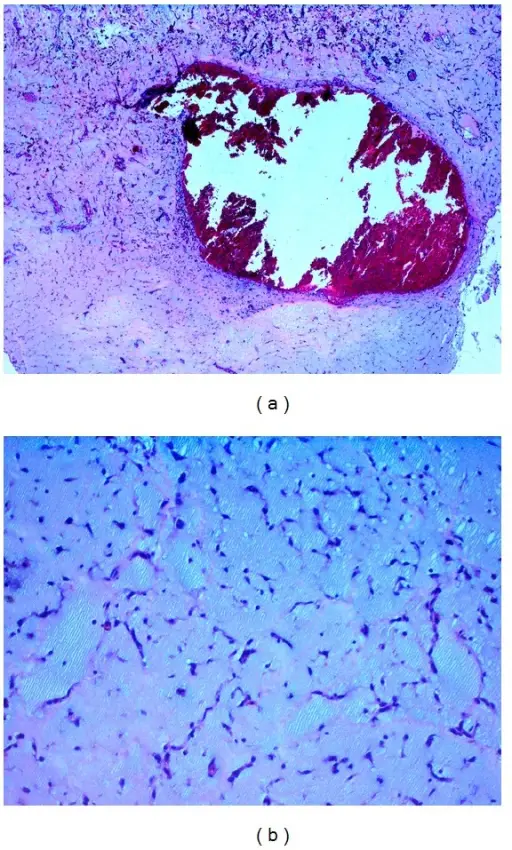

Myxomas typically appear as pedunculated masses in the left atrium on imaging.

Myxomas may causes syncope by blockage the mitral valve.

Myxomas typically have a histologic appearance showing an abundance of ground substance and a gelatinous appearance.